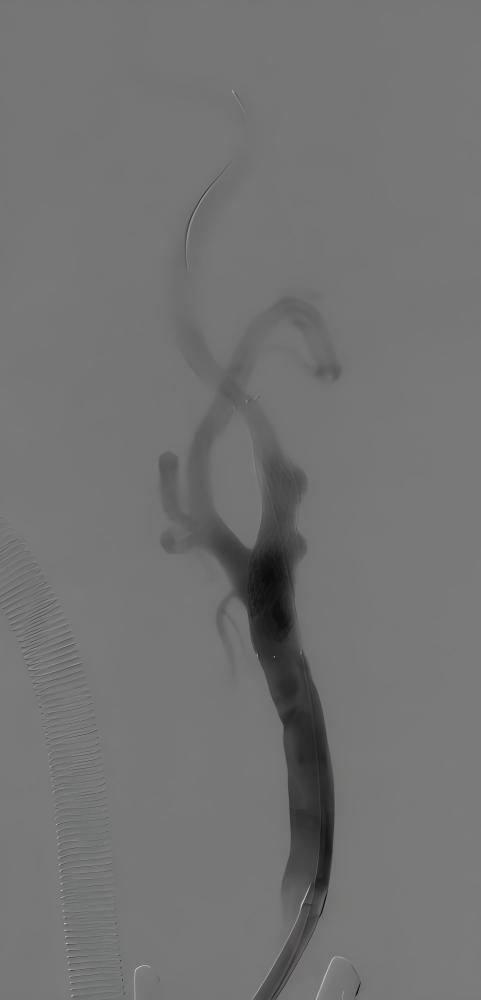

据悉,患者张某(化姓)因反复头晕就诊,检查后确诊为左侧颈内动脉重度狭窄,且主动脉弓为III型弓,颈总动脉明显迂曲,且左侧颈动脉分叉位置较高,属于颈动脉狭窄治疗中较为复杂的解剖类型。若采用传统经股动脉颈动脉支架置入术,导管通过主动脉弓及扭曲血管难度大,脑栓塞风险高;若行颈动脉内膜剥脱术,则会因为分叉位置高、术野暴露困难,手术创伤和技术难度也明显增加。

针对患者复杂病情,烟台毓璜顶医院血管外科团队在车海杰主任的带领下,开展了多轮术前讨论。在与患者及家属充分沟通后,最终确定采用国际前沿的TCAR技术实施治疗。手术当天,团队通过颈部小切口精准暴露颈总动脉,快速建立反转脑血流保护系统,在全程有效脑保护下完成病变段支架精准植入。术中造影显示,患者狭窄的颈内动脉恢复通畅,支架位置贴合理想,脑部供血得到显著改善。术后患者恢复顺利,无任何新发神经系统并发症,头晕等不适症状明显缓解,目前已顺利康复。

手术前后